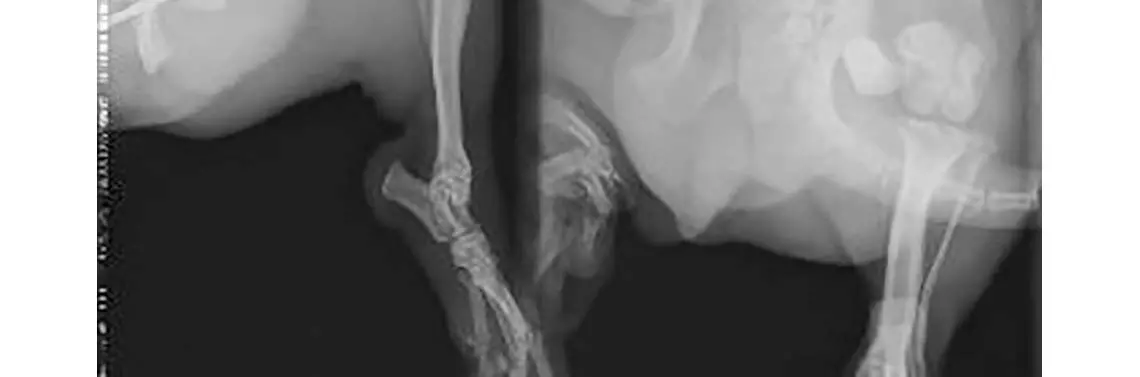

Została wykonana reoperacja, nastawiono odłamy i dołożono 2 skrzyżowane druty Kirschnera. Po 6 tygodniach wykonano kontrolne zdjęcie RTG (fot. 3), które uwidoczniło rozejście się odłamów oraz brak cech zrostu, przebudowę struktur kości udowej i odczyn okostnej odłamu bliższego, cechy osteolizy i ścieńczenie warstwy korowej odłamu dalszego. Zdecydowano o usunięciu gwoździ i pozostawieniu do samoistnego zagojenia.

RTG boczne i strzałkowe 8 dni po zabiegu – destabilizacja odłamów